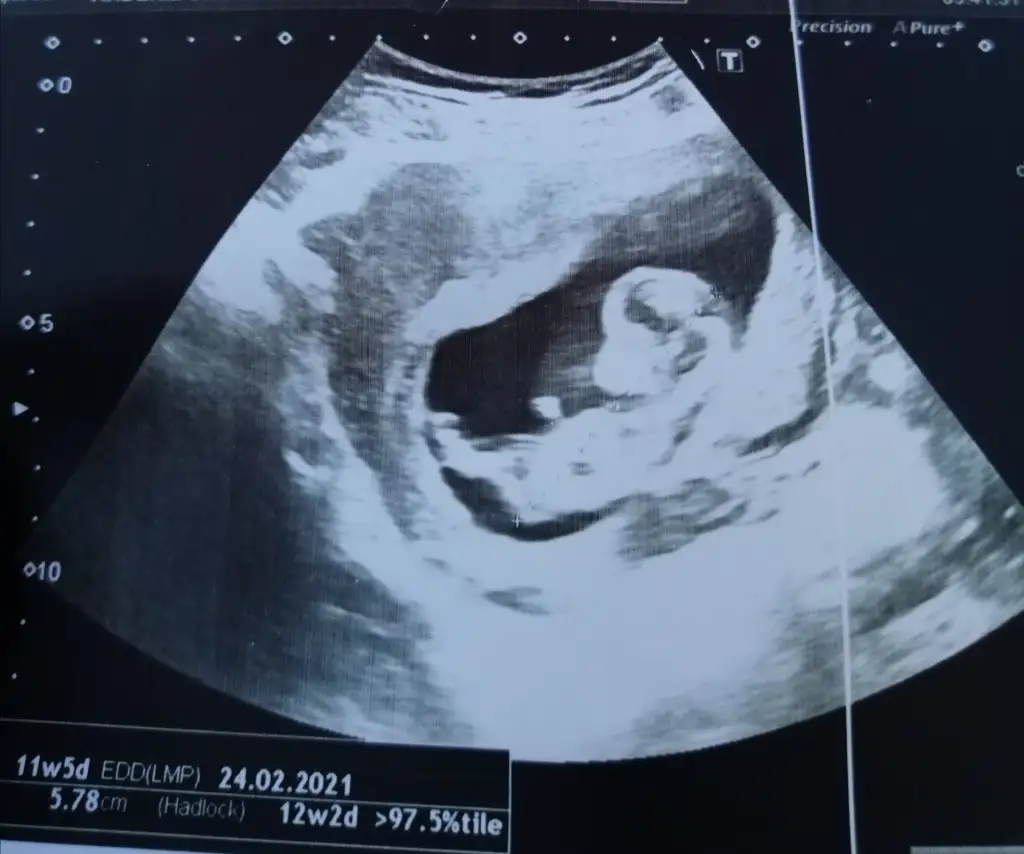

Erkek gibi sankiIkra meyra 14 hafta ama görebilir misiniz 12. Haftadaki ultrasonu doktor vermedi sağolsun.

Yazmamışım 11 +5Ikra meyra bana da yorum yapar mısın rica etsem

Kız sanki net değil USGIkra meyra bana da yorum yapar mısın rica etsem

Kaç haftalık 11 12 13 haftalar olmalıBenim bebisime de bakar misiniz cok merak ediyorum.

Önden gidiyor 11+4 dedi doktorum ama cinsiyetiyle ilgili bisey soylemedi maalesef. Burda cok tavsiye eden olmus seni bende hemen sana sormak iatedim canim.Kaç haftalık 11 12 13 haftalar olmalı